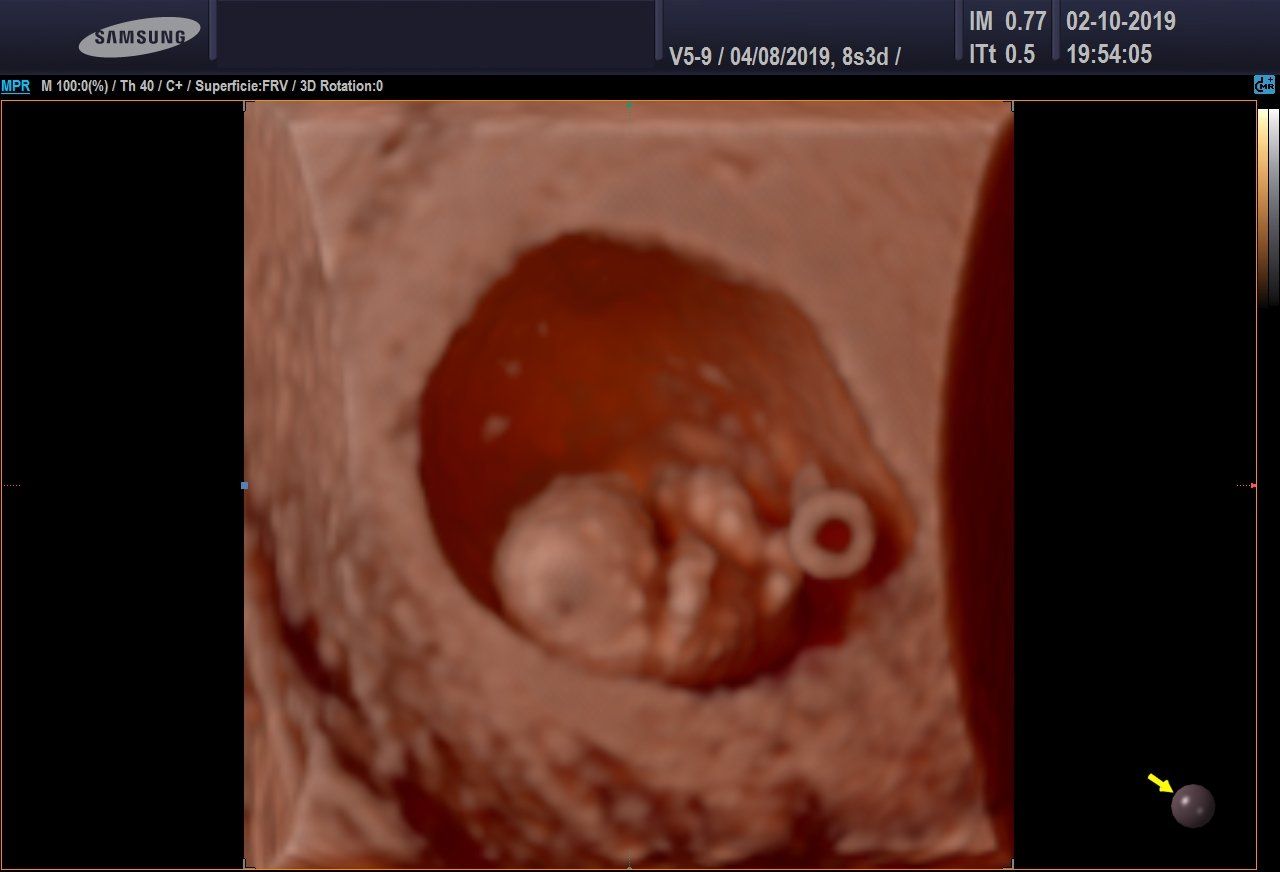

Ecografia 3D/4D

L'ecografia 3D consente di ottenere delle immagini statiche, non in movimento, ma in pratica delle foto delle fattezze del feto.

È in atto il metodo più attendibile e non invasivo nel corso della gravidanza per valutare il rischio di avere un bimbo con un problema cromosomico, come per esempio la Sindrome di Down.